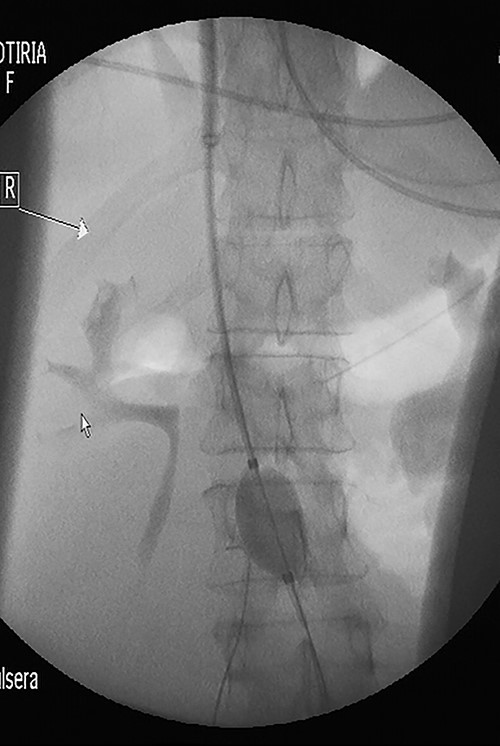

Under fluoroscopy, an aortic occlusion balloon catheter (Reliant AB46 Medtronic Minneapolis, SENSH 1228 W) through a 12F introducer sheath was inserted to the right internal jugular vein into the IVC and was positioned in the restricted free inferior caval space just below the renal veins (Fig. 3). Before the final placement of the balloon and the initiation of any surgical procedure, the hemodynamic condition of the patient was checked during the placement and extension of the balloon. No hemodynamic instability was observed, so the operation proceeded to the next step. The catheter balloon was inflated with the appropriate volume of physiologic saline solution to occlude the IVC and the operation began. The temporal vena cava occlusion continued until the fibroid mobilization and the proximal control of the thrombosed left common iliac vein. After mass mobilization, the vena cava was checked manually for possible clots within the vein, coming from the common iliac veins, especially from the left one. Following removal of the fibroids with the uterus, the occlusion balloon was deflated and removed without any complication. The blood pressure and heart rate were monitored continuously throughout the operation; no significant changes occurred. A total hysterectomy with bilateral adnexectomy was also conducted.

Under fluoroscopy, an aortic occlusion balloon catheter was positioned in the restricted free inferior caval space just below the renal veins.